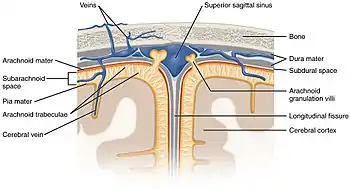

The ventricles are filled with cerebrospinal fluid (CSF) which bathes and cushions the brain and spinal cord within their bony confines. CSF is produced by modified ependymal cells of the choroid plexus found in all components of the ventricular system except for the cerebral aqueduct and the posterior and anterior horns of the lateral ventricles. CSF flows from the lateral ventricles via the interventricular foramina into the third ventricle, and then the fourth ventricle via the cerebral aqueduct in the midbrain. From the fourth ventricle it can pass into the central canal of the spinal cord or into the subarachnoid cisterns via three small foramina: the central median aperture and the two lateral apertures. According to the traditional understanding of cerebrospinal fluid (CSF) physiology, the majority of CSF is produced by the choroid plexus, circulates through the ventricles, the cisterns, and the subarachnoid space to be absorbed into the blood by the arachnoid villi.

The fluid then flows around the superior sagittal sinus to be reabsorbed via the arachnoid granulations (or arachnoid villi) into the venous sinuses, after which it passes through the jugular vein and major venous system. CSF within the spinal cord can flow all the way down to the lumbar cistern at the end of the cord around the cauda equina where lumbar punctures are performed.

The brain and spinal cord are covered by the meninges, the three protective membranes of the tough dura mater, the arachnoid mater and the pia mater. The cerebrospinal fluid (CSF) within the skull and spine provides further protection and also buoyancy, and is found in the subarachnoid space between the pia mater and the arachnoid mater.